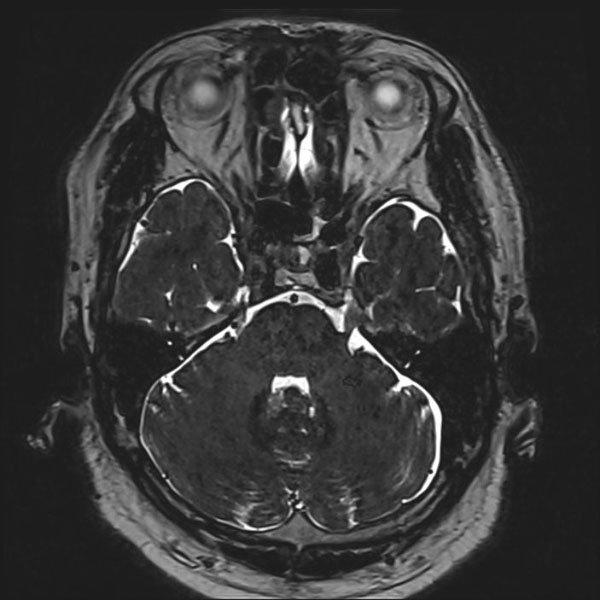

症例 '26年3月

No.

584

'26年3月

50代

三叉神経痛第3枝領域

術後血管撮影